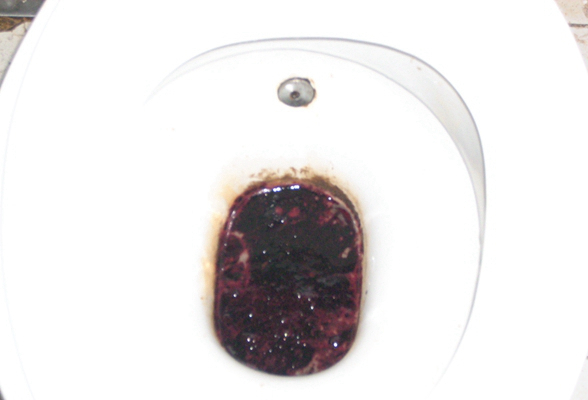

結腸癌症狀 (7)

結腸癌症狀 (8)

結腸癌症狀 (9)

結腸癌症狀 (49)

結腸癌症狀 (5)

結腸癌症狀 (50)

結腸癌症狀 (51)

結腸癌症狀 (6)